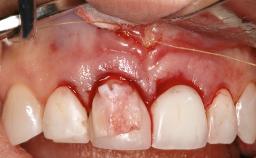

Treatment of Advanced Peri-Implantitis by Implant Removal Followed by Bone Reconstruction and New Implant Placement

Paolo Casentini and Matteo Chiapasco present a case in which the peri-implant defect was not suitable for a fully regenerative approach. It involves implant removal, use of a CAD/CAM customized titanium mesh in the grafting phase, and placement of new implants. A 62-year-old woman was referred for consultation regarding her implant-supported prosthesis replacing teeth 14 to 16. The patient’s main concern was pain and recurrent swelling in the right posterior maxilla. The patient also reported difficulty and discomfort when brushing the area. The patient reported she had been treated in another country, where she had received three implants in combination with sinus-floor augmentation for the replacement of the posterior maxillary teeth three years earlier. The patient indicated “endodontic complications” to be the reason for the extraction of the teeth.